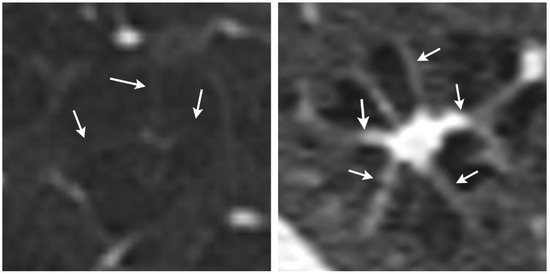

The Octopus Sign—A New HRCT Sign in Pulmonary Langerhans Cell Histiocytosis

Background: Fibrosis in pulmonary Langerhans cell histiocytosis (PLCH) histologically comprises a central scar with septal strands and associated airspace enlargement that produce an octopus-like appearance. The purpose of this study was to identify the octopus sign on high-resolution computed tomography (HRCT) images [...] Read more.

Background: Fibrosis in pulmonary Langerhans cell histiocytosis (PLCH) histologically comprises a central scar with septal strands and associated airspace enlargement that produce an octopus-like appearance. The purpose of this study was to identify the octopus sign on high-resolution computed tomography (HRCT) images to determine its frequency and distribution across stages of the disease. Methods: Fifty-seven patients with confirmed PLCH were included. Two experienced chest radiologists assessed disease stages as early, intermediate, or late, as well as the lung parenchyma for nodular, cystic, or fibrotic changes and for the presence of the octopus sign. Statistical analysis included Cohen’s kappa for interrater agreement and Fisher’s exact test for the frequency of the octopus sign. Results: Interobserver agreement was substantial for the octopus sign (kappa = 0.747). Significant differences in distribution of the octopus sign between stages 2 and 3 were found with more frequent octopus signs in stage 2 and fewer in stage 3. In addition, we only found the octopus sign in cases of nodular und cystic lung disease. Conclusions: The octopus sign in PLCH can be identified not only on histological images, but also on HRCT images. Its radiological presence seems to depend on the stage of PLCH. Full article